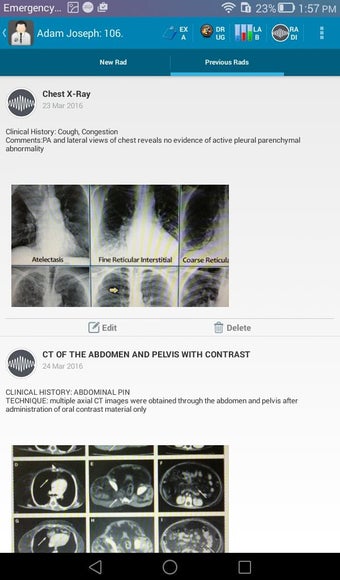

The Android Medical Records App by MedClin is a free medical records tracker app that allows users to store anamnesis, patient records, patient history, and health information. It is easy to use and provides numerous features such as username and password authentication, exporting medical data to Excel Sheet, and the ability to attach medical documents of any type. The app also has a smart search feature that allows users to search for patient information by name or ID, and even capture a photo for their profile.

In addition, the app has a blood pressure module that measures systolic, diastolic, and pulse, and allows users to export blood pressure reports to either PDF or graphs. The app also has a blood glucose (sugar) module that records blood sugar values and allows users to export blood glucose reports to either PDF or graphs. Users can also send blood pressure and blood sugar reports to their doctor. The app is compatible with multiple screens, including phones and tablets, and works on Chromebook systems. Overall, the Android Medical Records App is a great tool for patients and physicians alike for managing patient information and medical records.